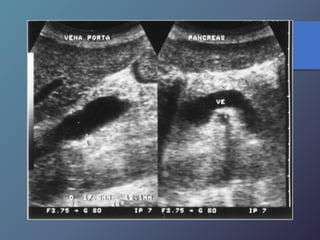

Anomalías Vasculares

• Presión normal de la porta: 5-10mmhg (14cm de agua).

• Se define como presión directa de la vena porta superior a

10mmhg.

• Puede dividirse en pre sinusoidal cuya causa mas frecuente

es la trombosis de la vena porta o esplénica.

• La cirrosis es la causa mas frecuente de hipertensión portal

intrahepatica.

• Características ecográficas: signos secundarios de

esplenomegalia, ascitis, colaterales venosas porto sistémicas.

• Se produce un aumento igual o mayor a 1.3cm.

Hipertensión Portal:

Anomalías Vasculares • Presiónnormal de la porta: 5-10mmhg (14cm de agua). • Se define como presión directa de la vena porta superior a 10mmhg. • Puede dividirse en pre sinusoidal cuya causa mas frecuente es la trombosis de la vena porta o esplénica. • La cirrosis es la causa mas frecuente de hipertensión portal intrahepatica. • Características ecográficas: signos secundarios de esplenomegalia, ascitis, colaterales venosas porto sistémicas. • Se produce un aumento igual o mayor a 1.3cm. Hipertensión Portal: